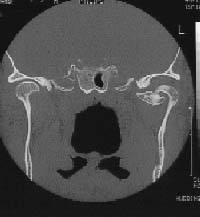

The produced images are cross-sectional and their pattern (figure 2) can be compared with slices of a loaf of bread. The examination time depends upon area of the body being viewed and can be from 15-20 minutes to 2 or 3 hours. Patients who cannot lie still for that period of time require sedation to help them being motionless.

Figure 2: A frontal or coronal slice through the temporomandibular joint area of the skull. An osteochondroma can be seen in the left medial side of caput mandible.